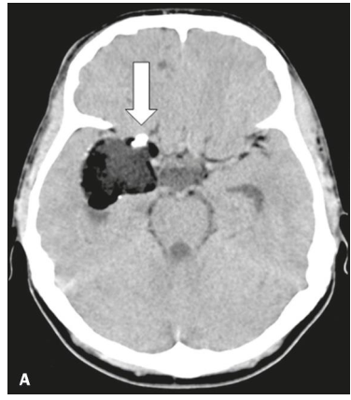

Observe a tomografia, abaixo:

O processo expansivo, demonstrado à imagem, é característico de:

cisto dermoide.

cisto odontogênico.

adenocarcinoma invasivo.

meningoangiomatose hamartomatosa hemorrágica.

meningoangiomatose hamartomatosa isquêmica.